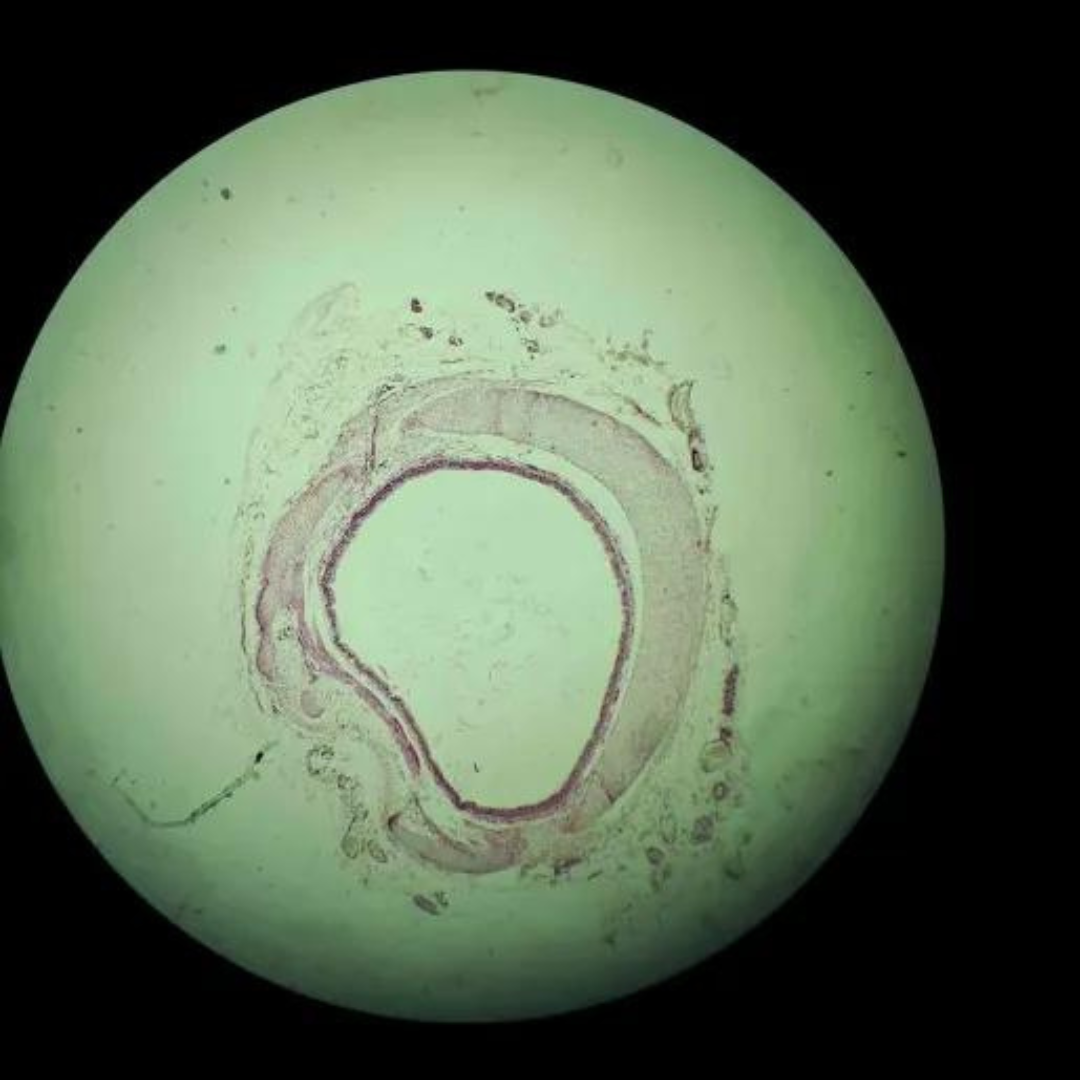

Muscular Arteries (Medium Sized Arteries)

Muscular Arteries (Medium Sized Arteries)

Muscular Arteries (Medium Sized Arteries)